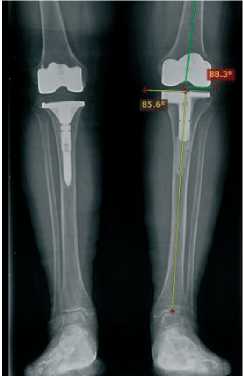

Послеоперационный контроль . На следующий день выполняются рентгенограммы для оценки восстановления механической оси и точности позиционирования компонентов в фронтальной плоскости (рис. 4).

Рисунок 4. Постуральная рентгенограмма после операции